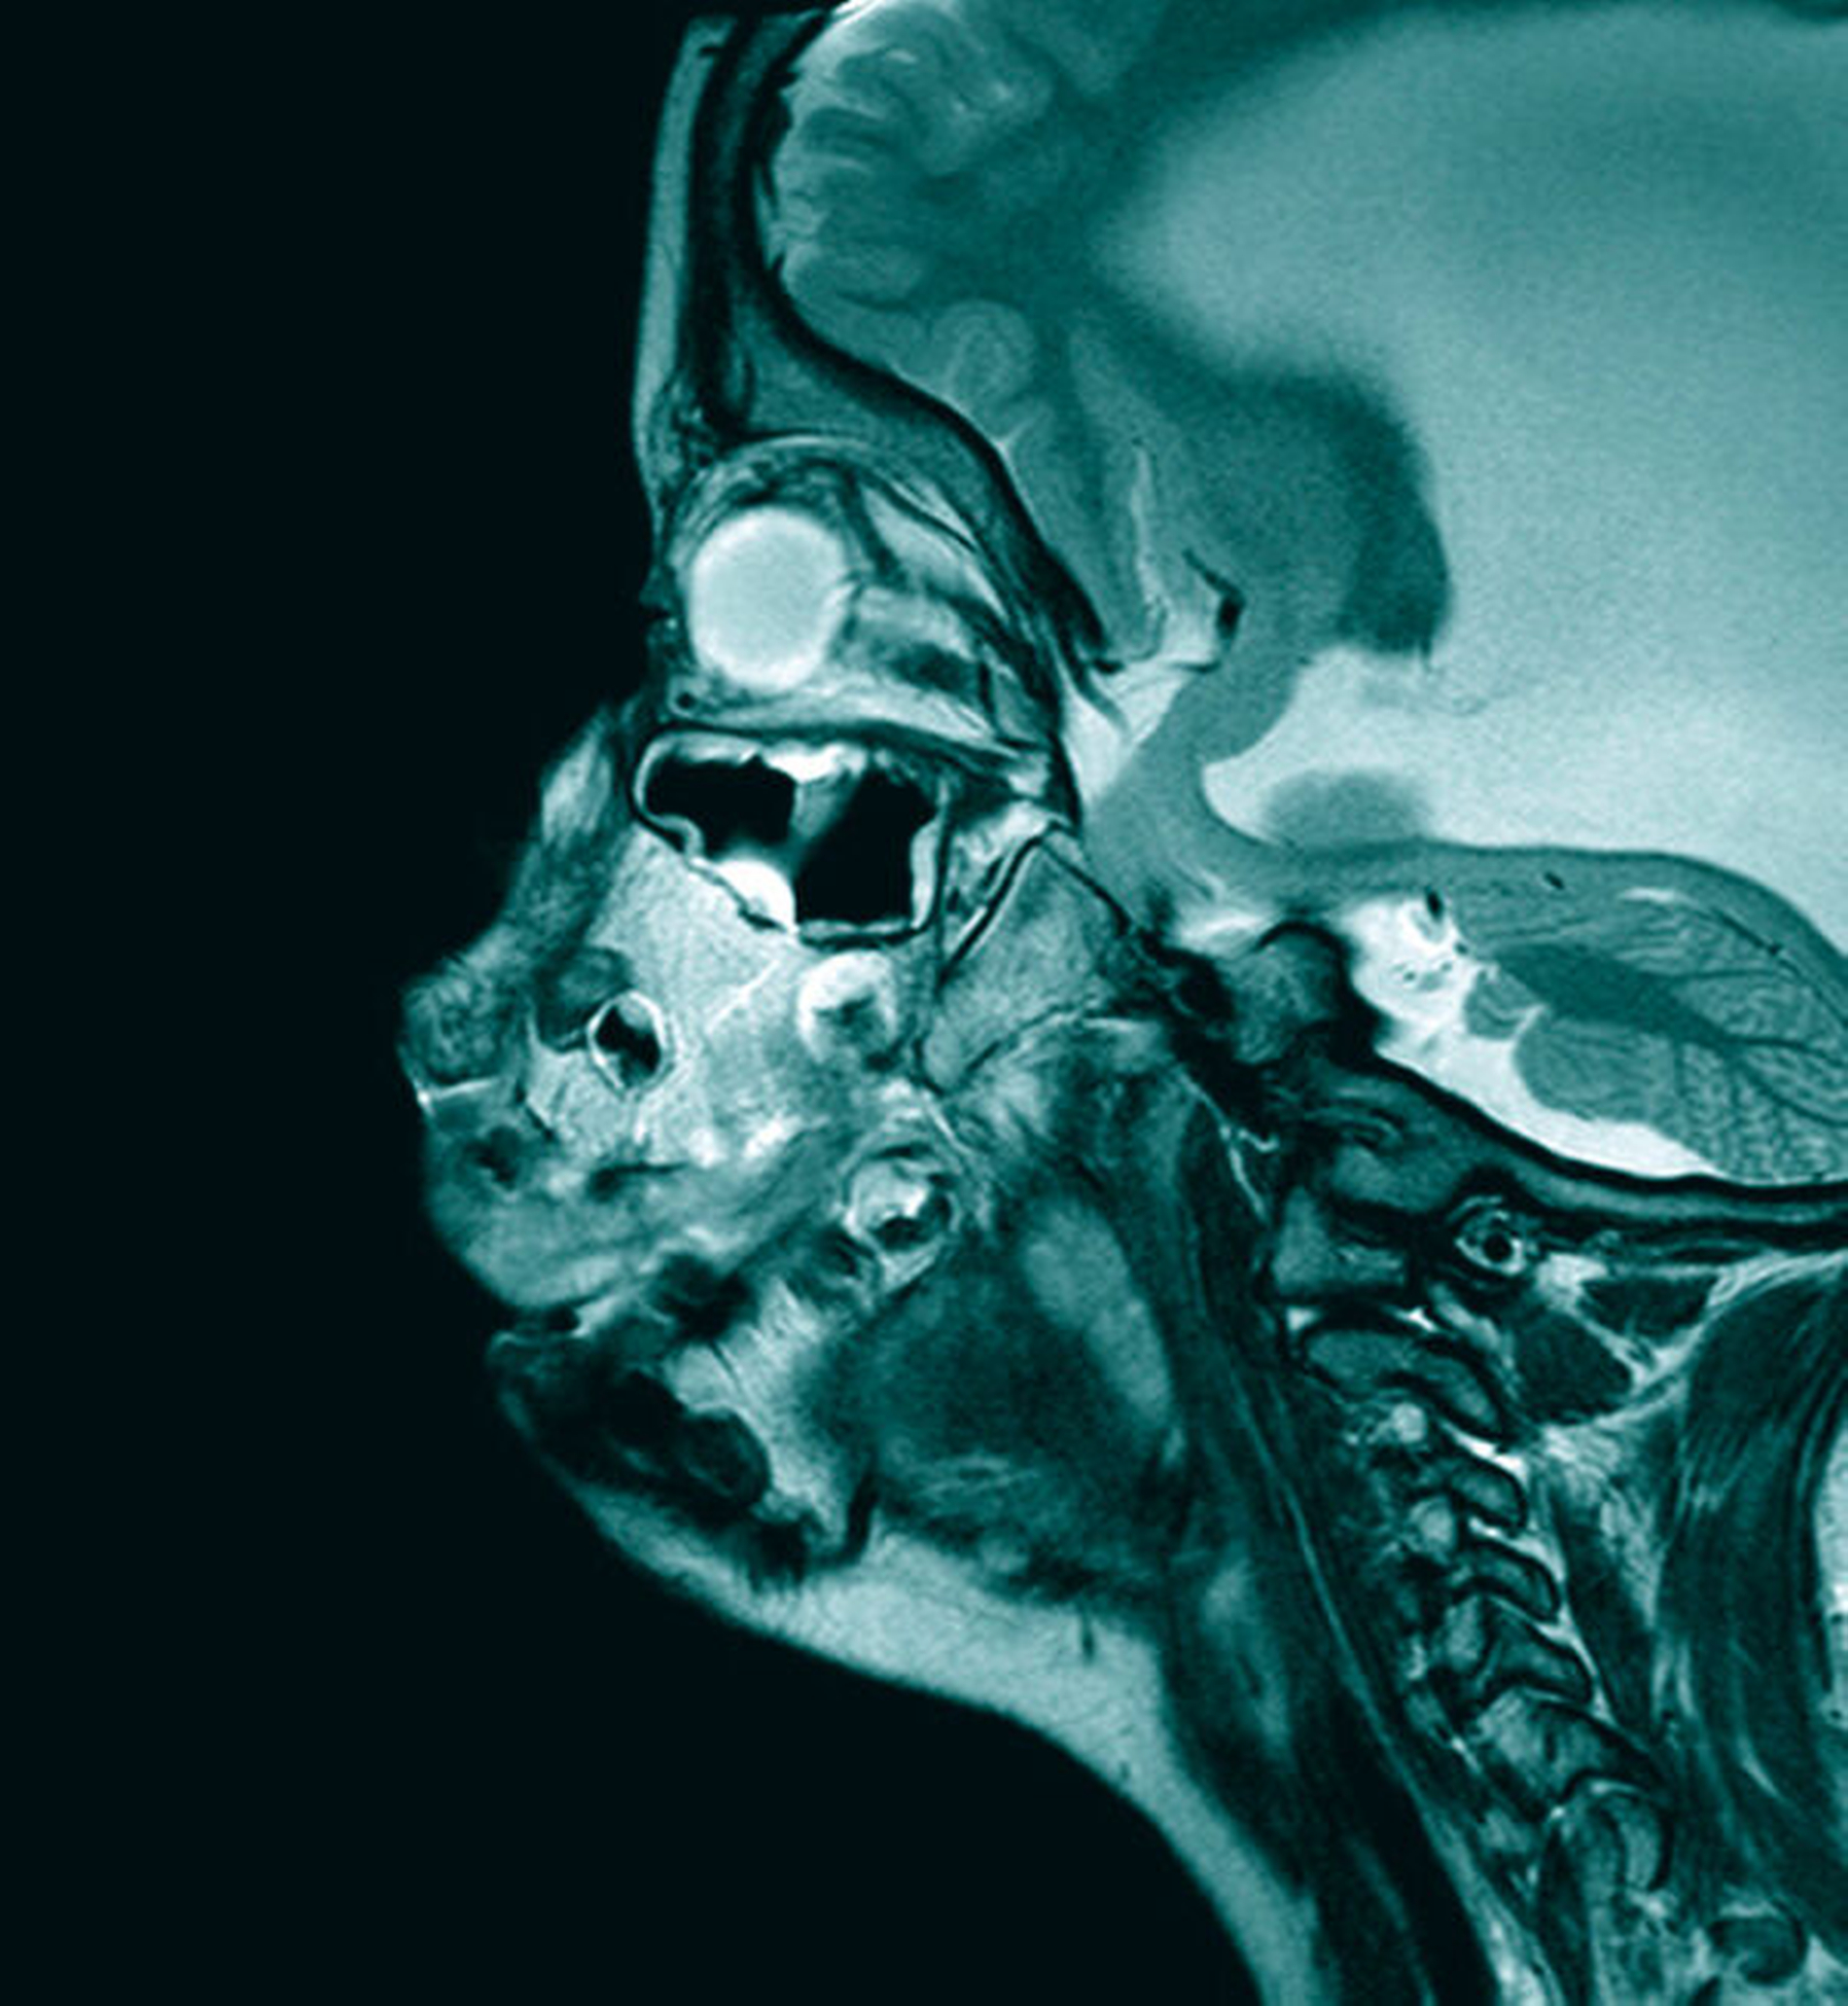

Aufgrund der eingeschränkten Möglichkeit der klinischen Untersuchung erfolgte zur weiteren Diagnostik zunächst eine Magnetresonanztomografie in Intubationsnarkose. Hier zeigten sich Deformationen des knöchernen und des weichgewebigen Ober- und Unterkiefers sowie eine fast vollständige Verlegung der Mundhöhle im Rahmen der bestehenden Gingivahyperplasie im Bereich der Front- und der Eckzähne der Maxilla sowie der Rami mandibulae beidseits. Die Zunge wurde durch die Raumforderung in den Mundboden verlagert.

Neben der Vergrößerung der knöchernen maxillären Strukturen zeigte sich die Gingiva ebenfalls massiv hypertrophiert. Dies prägte auch das klinische Bild. Hinzu kam eine ausgeprägte Medialisierung der Rami mandibulae, die ebenfalls von deutlichen Gingivahyperplasien überzogen waren und sich in der Mitte der Mundhöhle großflächig berührten. Die Zähne in Ober- und Unterkiefer wiesen Fehlstellungen auf und waren zum Teil vollständig von den Hyperplasien überwuchert. In der Gesamtschau ergab sich eine deutliche Reduktion der Mundhöhle, so dass bei einer Progredienz des Wachstums dieser Raumforderungen von einer vitalen Bedrohung durch eine Verlegung der Atemwege auszugehen war.

In Vollnarkose erfolgte eine gründliche klinische Inspektion. Diese zeigte ein noch massiveres Ausmaß der Gingivawucherungen als durch die radiologische Diagnostik und die klinische Untersuchung vermutet. Der Zungenraum war durch die Raumforderung stark eingeengt und die Zunge lag funktionseingeschränkt in den Mundboden – in einer Art Hohlraum – verlegt, umgeben von den Gingivawucherungen des Unterkiefers.